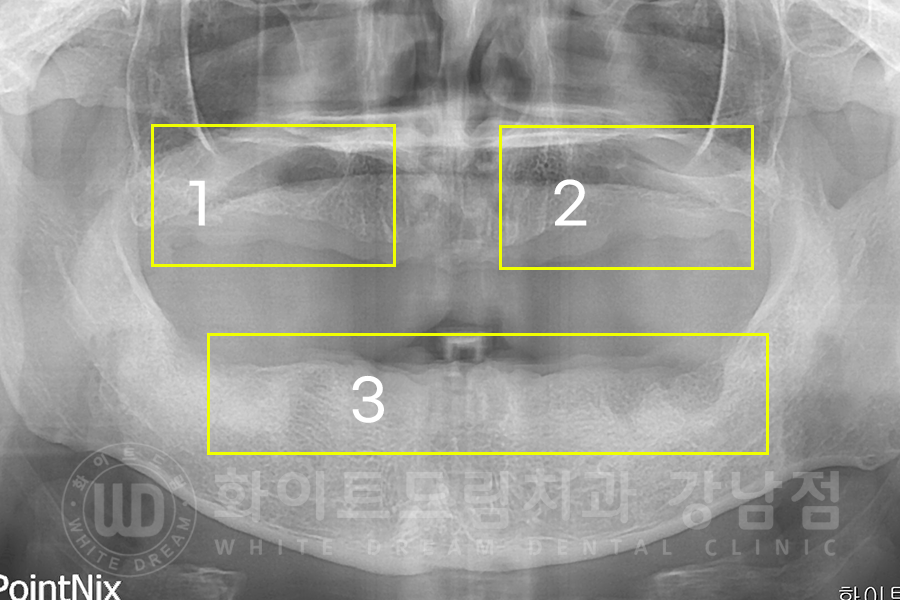

▲ 전악 발치 후 환자분 x-ray 사진입니다. (17.06.03)

1), 2) 상악 치조골은 임플란트를 심기에 뼈의 양이 많이 모자란 상태이기 때문에

뺨 쪽 잇몸에 작은 창을 내어 대량의 뼈이식을 진행하는 lateral 상악동 거상술을 이용하여 진행하기로 했습니다.

일반적으로 진행하는 crestal 방식보다는 붓기나 출혈, 통증이 조금 더 있을 수 있지만

한 번의 수술로 대량의 뼈이식재를 넣을 수 있다는 장점을 가지고 있습니다.